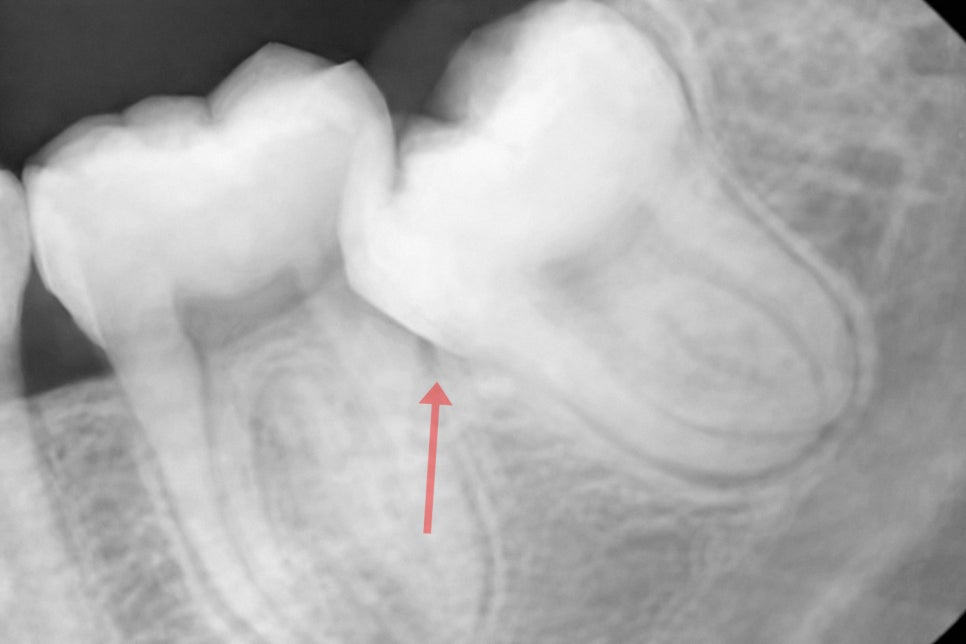

제일 빈번한 합병증은 인접치 우식으로

잇몸에 가려진 인접면에서 시작되어

이곳은 타액에 의한 자정작용이

되지 못할 뿐만 아니라

환자가 육안으로 확인하기 어렵고

근관에 근접할 정도로 우식이 깊어지기 전까지는

통증이 없는 경우도 많습니다.

따라서 환자가 시린 느낌이나 통증을 느껴

내원했을 때는 이미 치수의 감염이

진행된 경우가 대다수이며

치근과 맞닿아있는 경우에는

법랑질-시멘트 경계(CEJ) 부근이나

그 하방의 치근면에서 시작되며

이곳은 법랑질보다 무르고 두께가 얇아

산에 의한 부식에 취약해

상아질을 타고 순식간에 치수까지 도달하게 됩니다.

심한 경우 결국 제2대구치까지

발치해야 되는 최악의 상황으로 이어지기도 합니다.